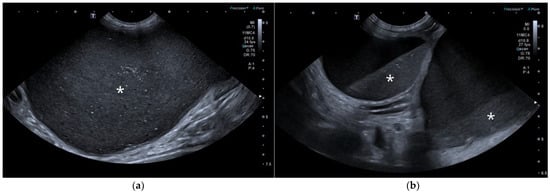

AUS in all three dogs revealed a fluid-filled cavitary structure originating in the caudal peritoneum between the colon and urinary bladder and extending cranially through the mid-abdomen, causing a mass effect. In cases 1 and 2, the lesion continued bilaterally as paired, thin tubular extensions coursing caudally through the inguinal rings adjacent to each testis (Figure 1a). In case 1, a focal mural narrowing resembling a uterine cervix was noted caudally (Figure 1b). The wall was thin and smooth in case 1, while in case 2 it was irregular, especially in its caudal aspect (Figure 2a,b). No information was available regarding the course of the UM horns or wall appearance for case 3. The luminal content consisted of echogenic, inhomogeneous fluid in all cases (Figure 3a); in case 2, sedimentation created fluid–fluid levels (Figure 3b).

Figure 1. Abdominal ultrasound (AUS) of case 1: (a) Oblique view of a uterine horn (arrowheads) within the scrotum, with the testis in the center (asterisk) and the epididymis on the right side of the image; (b) Longitudinal view of the caudal aspect of the uterus masculinus (UM) showing a focal cervix-like mural narrowing ventral to the descending colon (arrows).